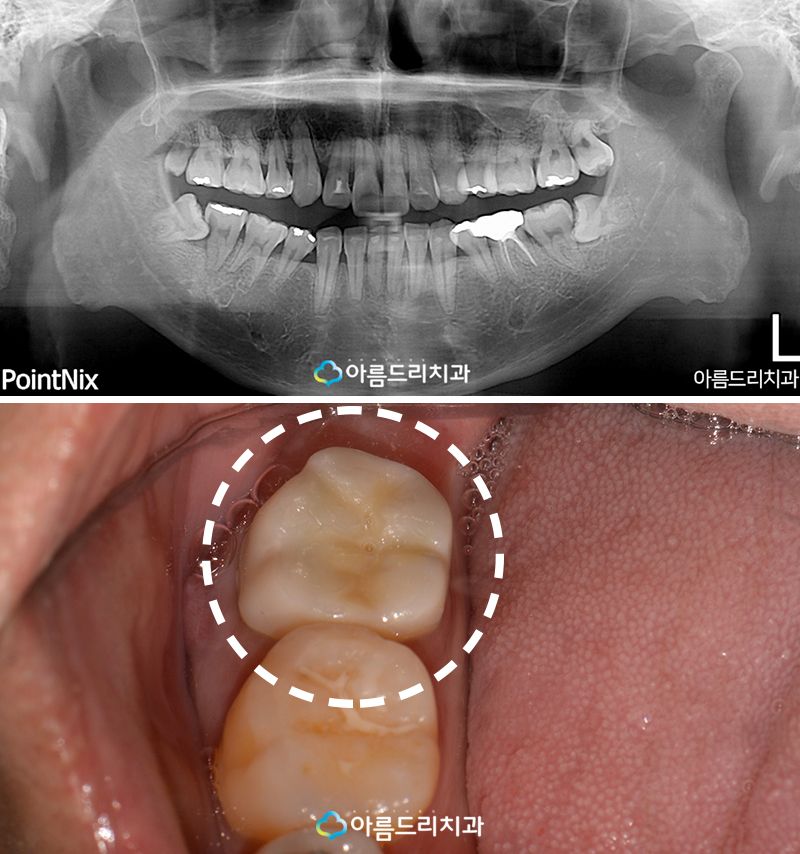

우측에 있는 사랑니쪽에 극심한 통증을 호소 하며 찾은 환자분의 엑스레이 사진을 찍어보니 좌측과 우측 모두 매복사랑니가 있었는데 매복 사랑니의 경우 인접한 치아에 문제를 발생시키 는 주요한 원인이 되기 때문에 발치를 하는 것 이 불가피 하였으며 가장 큰 문제는 바로 그 앞 인접해 있는 어금니에 문제가 있어보입니다.

어떠한 문제가 있는지 여러분들도 보실 수 있 게 엑스레이 사진을 한번 확대해 보았습니다.

매복사랑니의 경우 예전에 블로그에 자세하게 포스팅을 했었는데 매복된 각도와 정도에 따라 그 종류가 다양하게 분류되고 있으며 인접한 치아에 충치 혹은 치주(잇몸)의 문제 등을 야 기할 수 있기 때문에 발치를 권해드립니다.

환자분께서는 이 매복사랑니 때문에 통증이 심하다고 알고 계셨으나 그것이 아니라 바로 앞에 있는 어금니를 보니 충치도 심한 상태 였으며 뿌리쪽을 보시면 다른 치아의 뿌리는 경계선이 뚜렸한데 비하여 문제의 어금니의 뿌리는 흐리고 검은 부분이 보이시죠? 바로 뿌리쪽에 염증이 생겨서 그런것입니다.